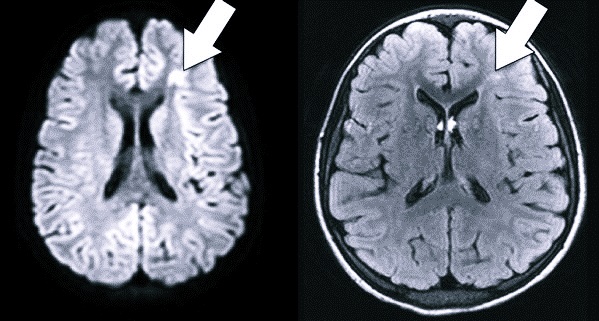

- Нейросонография (НСГ) – наличие в тканях головного мозга локальных очагов гиперэхогенности.

- Магнитно-резонансная томография (МРТ) – четко ограниченные очаги поражения паренхимы мозга.

- Компьютерная томография (КТ) – снижение плотности тканей в локальных очагах.

- Допплер энцефалограмма (ДЭГ) – у доношенных детей – признаки умеренного снижения скорости кровотока в средней мозговой артерии, а у недоношенных – в передней.

- На компьютерной томограмме – очаговое снижение плотности паренхимы, ликворные пространства значительно сужены.

- МРТ – выраженные паренхиматозные поражения.

- На допплер энцефалограмме – магистральные артерии головного мозга парализованы, стойкое снижение скорости кровотока (гипоперфузия).